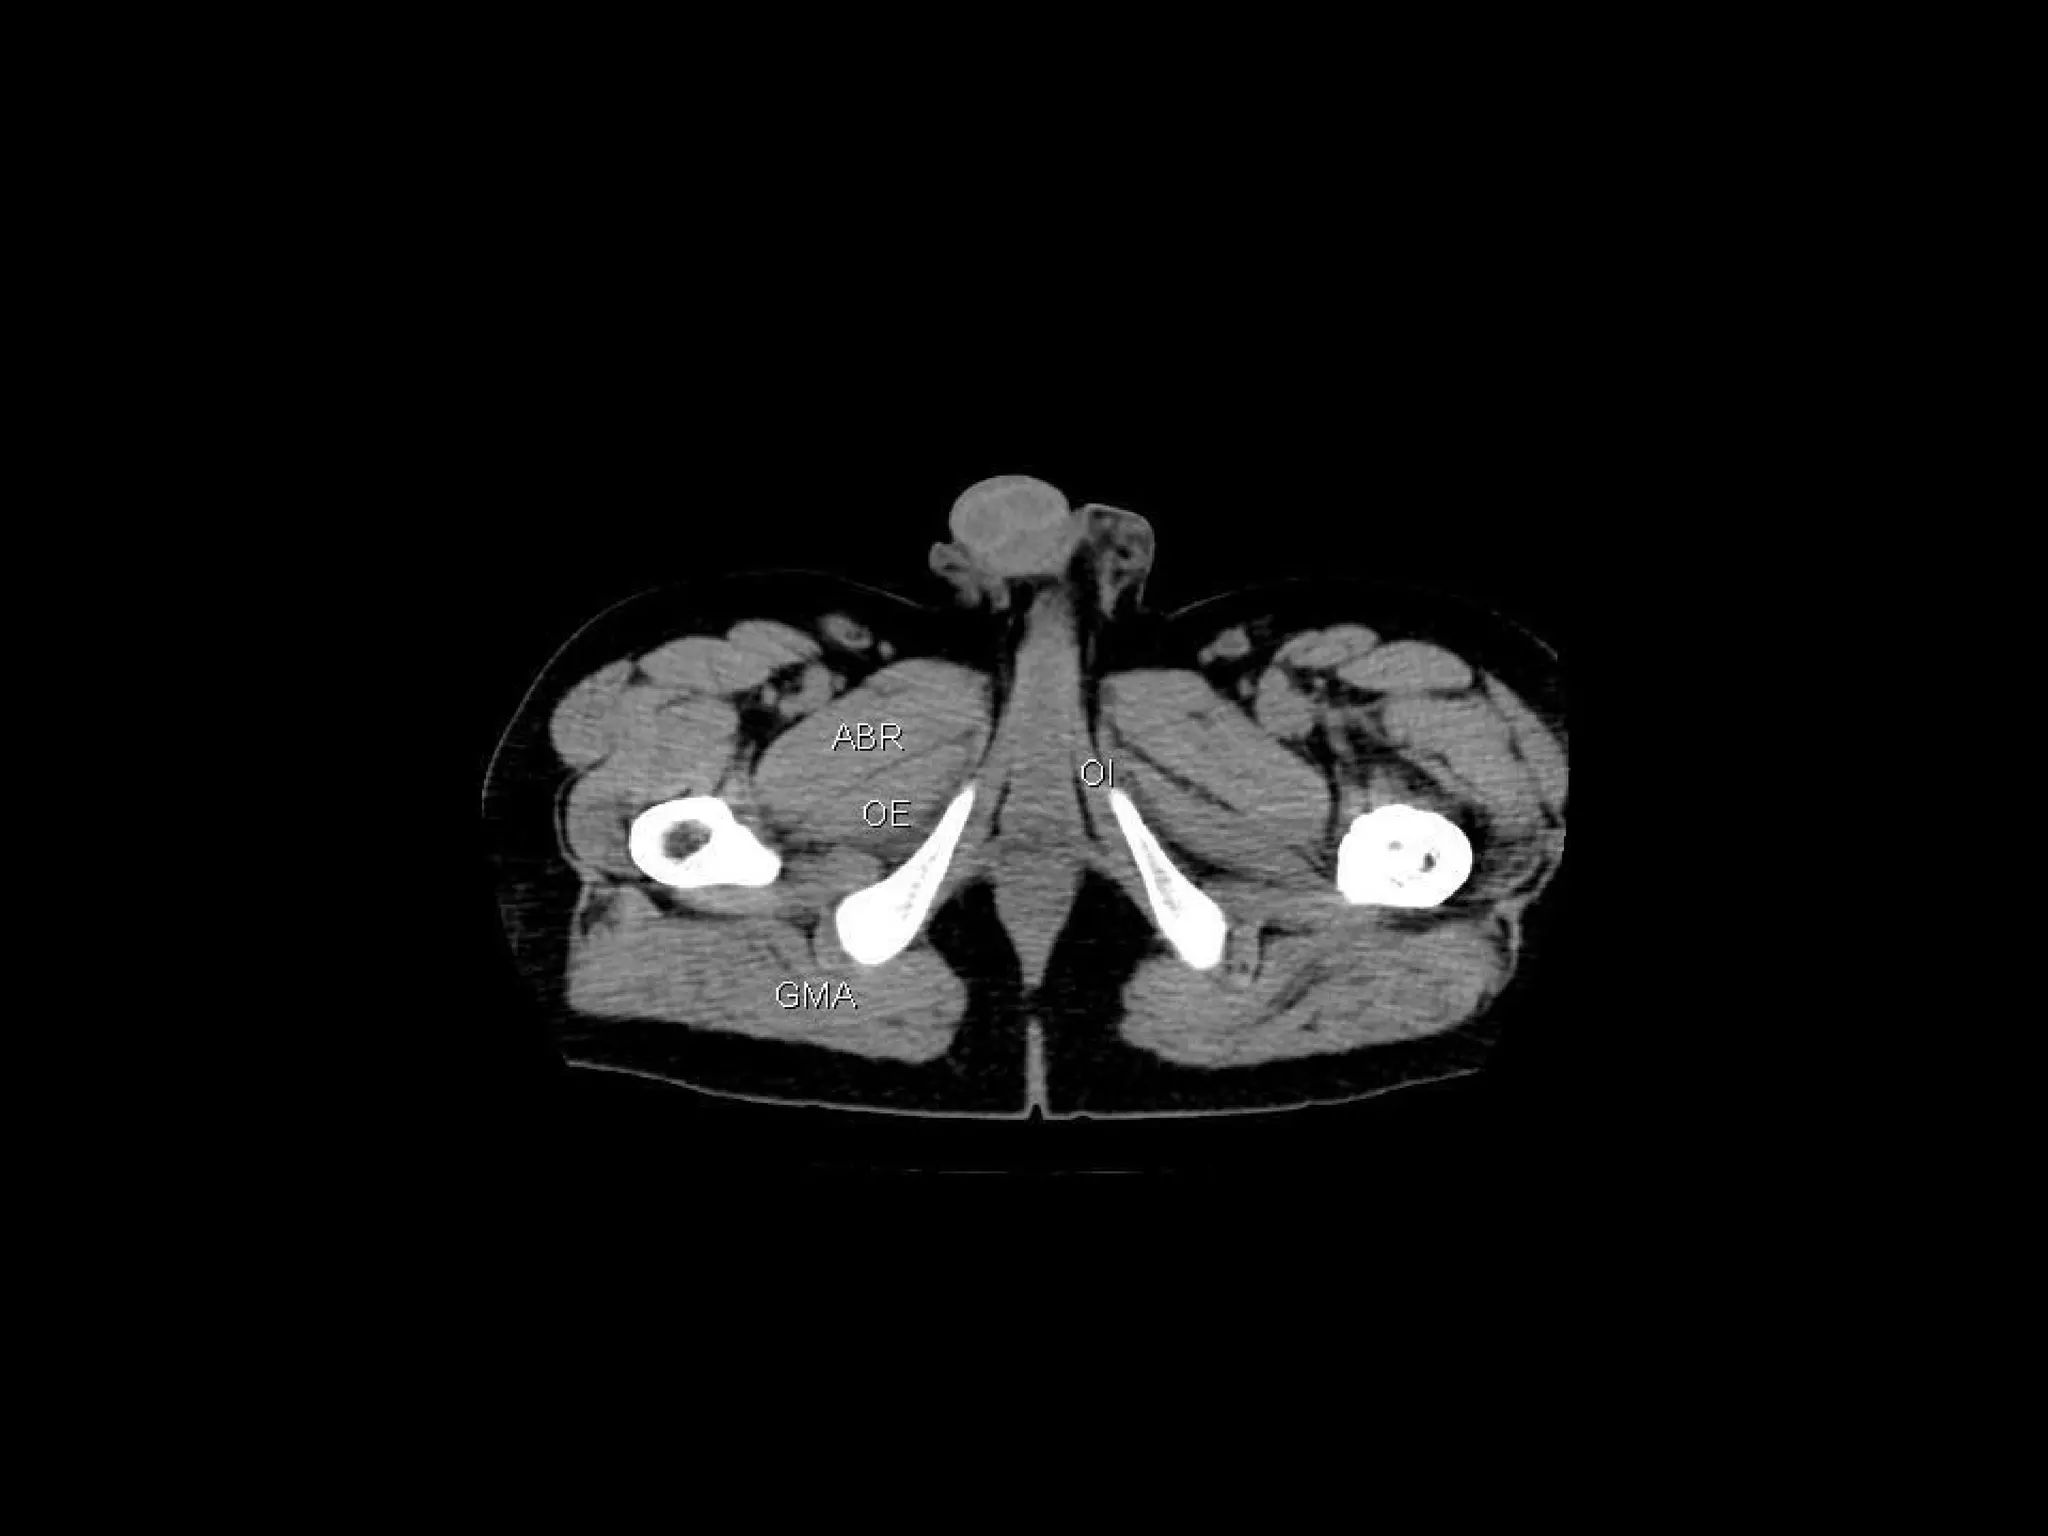

Radiographers are medical professionals who perform diagnostic imaging examinations and procedures to help physicians diagnose and treat diseases. They work under the supervision of radiologists to operate X-ray, CT, MRI, ultrasound and other medical imaging equipment and must have a strong understanding of human anatomy and pathology. Radiographers are responsible for correctly positioning patients, ensuring proper imaging techniques are used, and evaluating the quality of the resulting images.